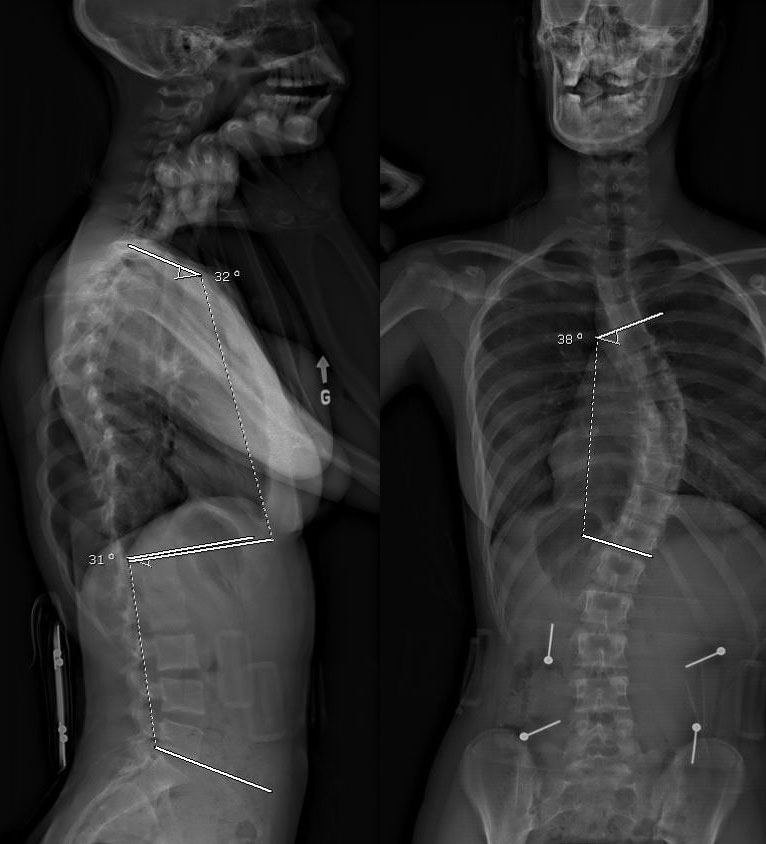

L’évaluation radiologique

L’évaluation radiologique consiste habituellement à prendre deux radiographies de la colonne vertébrale en entier, soit une de face et une de côté.